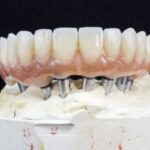

Implantat-Konstruktion im Oberkiefer mit bedingt abnehmbarer Brücke